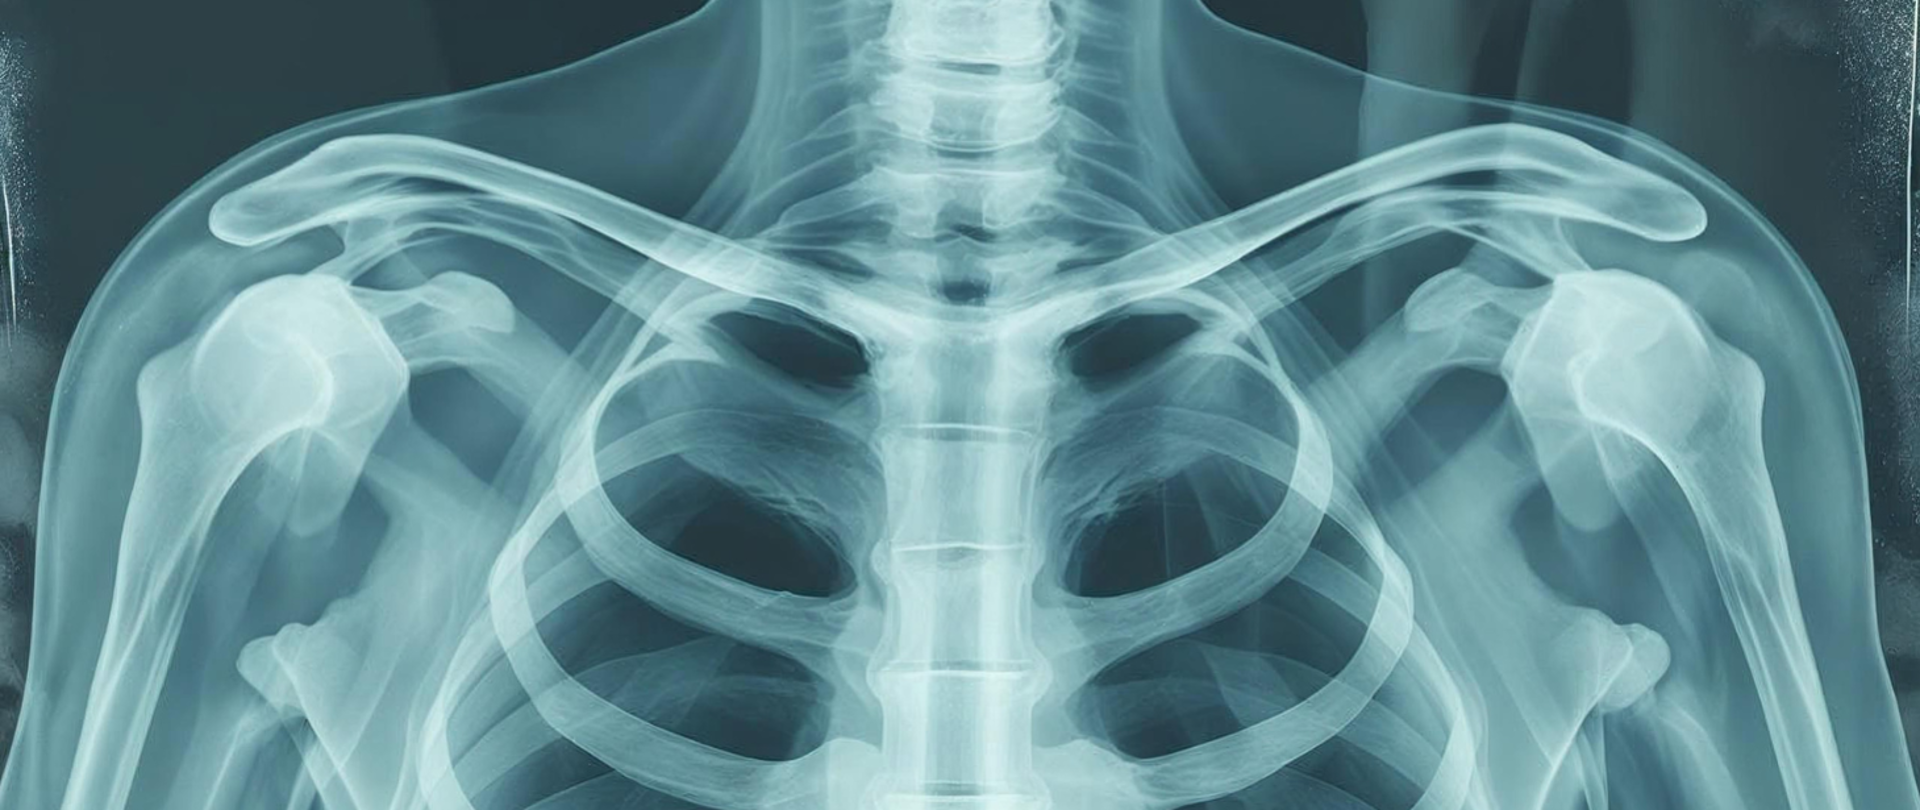

Światowy Dzień Radiologii 08.11.2025 Światowy Dzień Radiologii - Wojewódzka Stacja Sanitarno-Epidemiologiczna w Łodzi - Portal Gov.pl